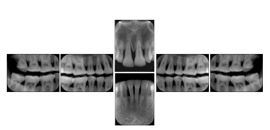

Intra-oral radiography typically involves acquisition of multiple images of various parts of the dentition. Many digital radiographic systems offer customized templates that are used for displaying the images in a study on the screen. These templates may also be referred to as mounts or view sets. The Structured Display Object represents a standard method of encoding and exchanging the layout and intended display of Structured Displays. A structured display object created in this manner could be stored with a study and exchanged with images to allow for complete reproduction of the original exam.

In most standard cases, images are oriented in structured layouts. These structured displays are useful to be shared between providers for reference purposes.

Table OO.1.1-1 shows structured display standard templates, where Viewset ID is based on the Japanese Society for Oral and Maxillofacial Radiology (JSOMR) classification provided by JIRA (Japan Medical Imaging and Radiological Systems Industries Association, www.jira-net.or.jp). Expected or typical teeth to be imaged location, region and designation codes are based on ISO 3950-2010, Dentistry - Designation system for teeth and areas of the oral cavity. For all the hanging protocols listed in OO.1.1-1, the value to use for Hanging Protocol Creator (0072,0008) is "JSOMR" and the value to use for Hanging Protocol Name (0072,0002) does not include "JSOMR" (e.g., "DL-S001A", not "JSOMR DL-S001A").